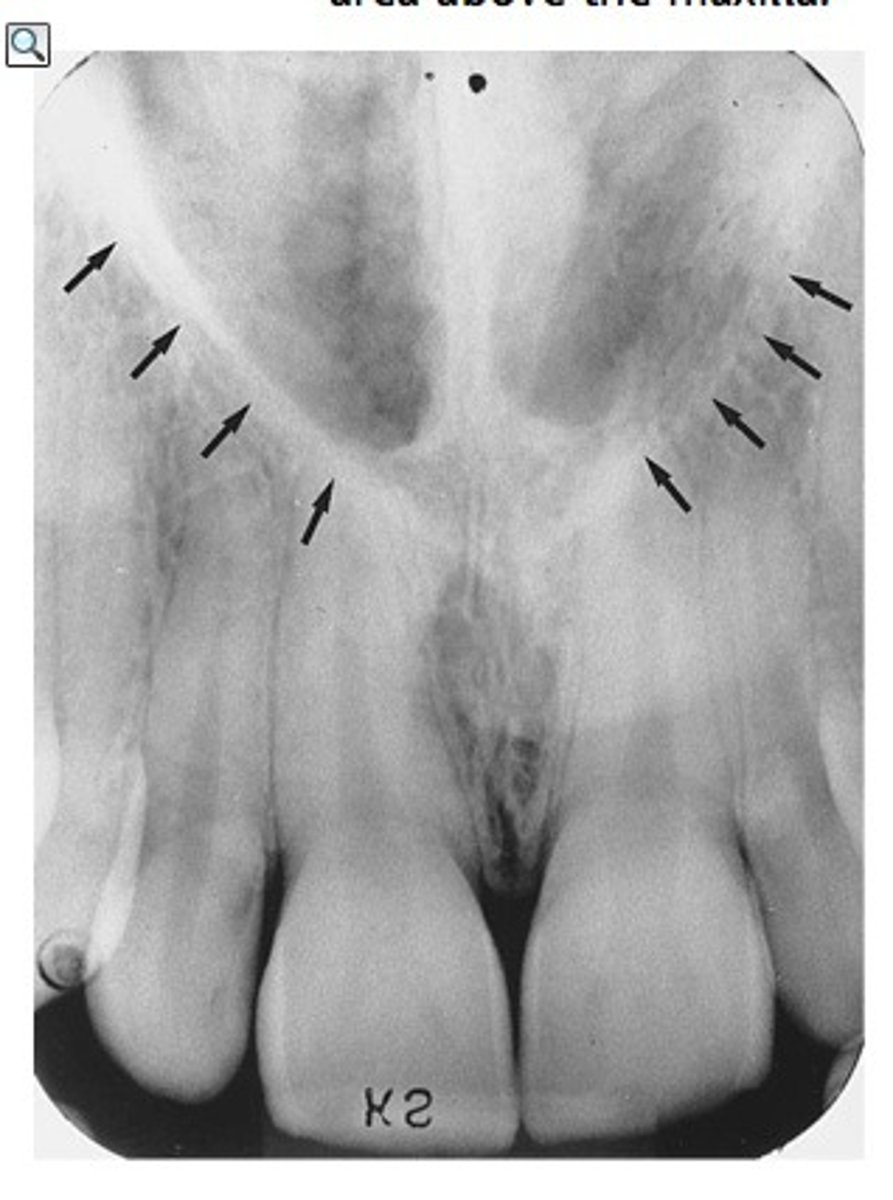

where can you see the nasal sinus in a radiograph

apices of 11/21

where can you see the nasal septum in a radiograph

where can you see the median palatine suture in a radiograph

line running the length of a palate

does the nasal sinus appear radiolucent or radiopaque in a radiograph

radiolucent

does the nasal septum appear radiolucent or radiopaque in a radiograph

radiopaque

does the median palatal suture appear radiolucent or radiopaque in a radiograph